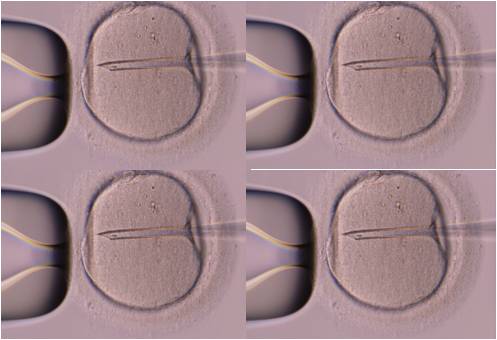

2012년 미국불임학회 (ASRM) P-414 The influence of working status and regular exercise on in vitro fertilization outcomes. (시험관 시술의 임신율과 직업과 규칙적인 운동이 어떤 영향을 주게 되는가?)

• 2014년 미국불임학회(ASRM) P-822 경미한 희소정자증을 보일 때 미세수정을 통한 시험관 시술이 반드시 필요한가?